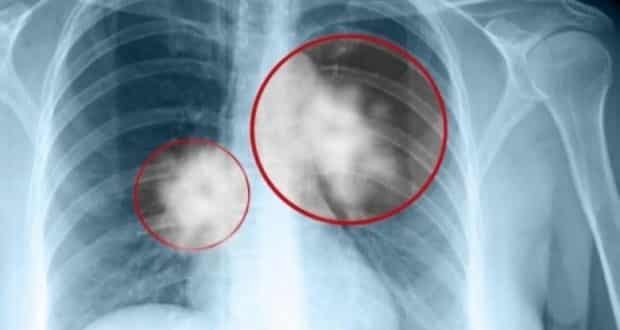

Το γεγονός ότι πέρασαν μόλις λίγοι μήνες από τη μεταμόσχευση μέχρι να εμφανιστούν οι πρώτες ανωμαλίες στις ακτινογραφίες υποδηλώνει ότι ο καρκίνος είχε ξεκινήσει όταν η δότρια ήταν ακόμη εν ζωή. Η ανάπτυξη των όγκων επιταχύνθηκε όμως από την ανασοκατασταλτική θεραπεία που λάμβανε η λήπτρια προκειμένου να μην απορρίψει το μόσχευμα.